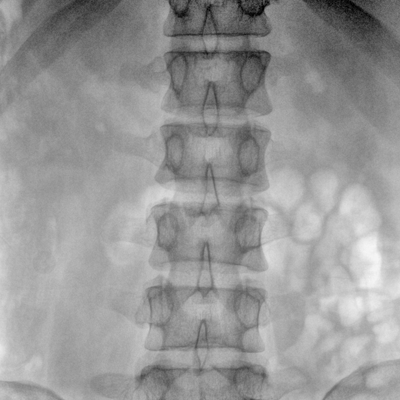

大尺寸動(dòng)態(tài)平板探測(cè)器,高DQE、低噪聲、圖像清晰。采用多分辨率圖像增強(qiáng)處理技術(shù),不同部位不同圖像處理算法,滿足客戶多樣化的需求。